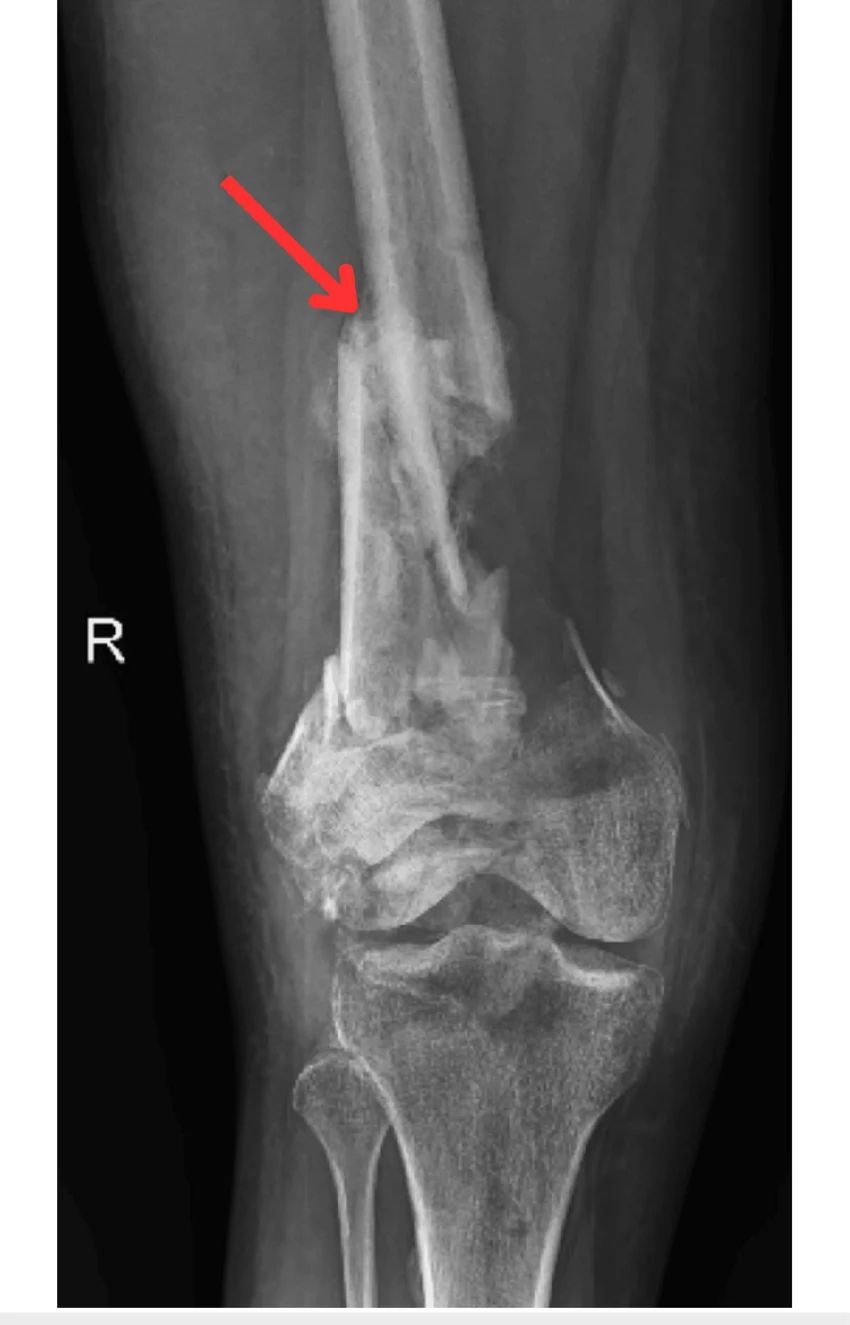

1. Complex or Multi-Fragment Fractures

When the fracture involves multiple bone fragments (comminuted fractures), achieving accurate alignment is critical. Robotic systems help reconstruct the joint surface precisely.

Robotic assisted knee surgery procedure image 2 Robotic assisted knee surgery procedure image 3 Robotic assisted knee surgery procedure image 4 Robotic assisted knee surgery procedure image 5